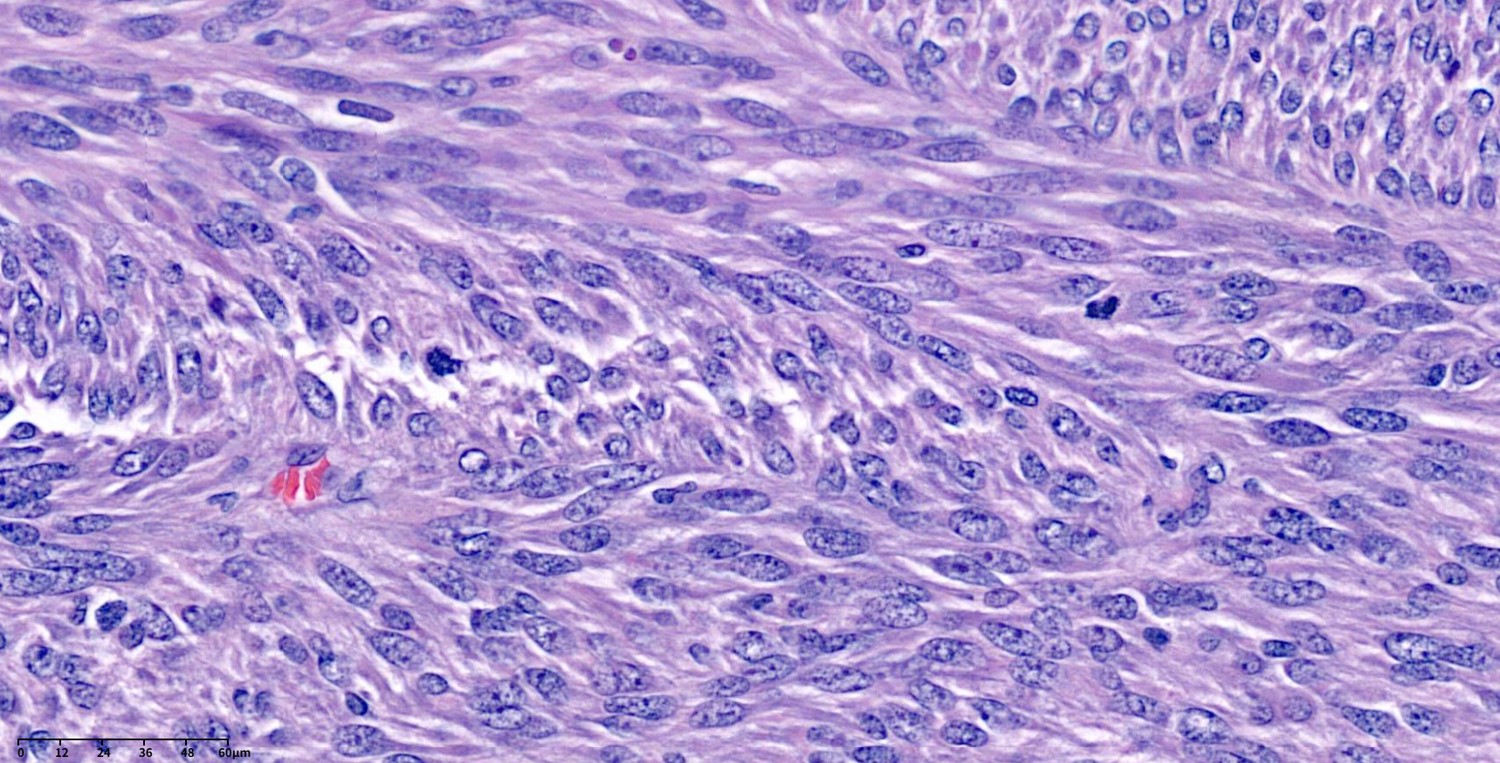

(1) Spindle: Bland spindle cells with faintly eosinophilic cytoplasm in a syncytial pattern; elongated nuclei with inconspicuous nucleoli; artifactual paranuclear vacuoles common in stomach GIST.

A, Spindle cell GIST composed of fascicles of uniform, bland cells with pale, eosinophilic cytoplasm.